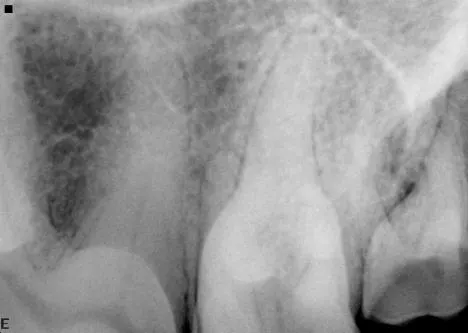

Dental images are best obtained with oral radiography techniques using dental film or a digital sensor and a dental x-ray machine. Locating the dental radiographic unit in the dental operatory makes it quick and easy to take dental radiographs. The film is placed intraorally in most instances to help eliminate overlap of structures. The tube head is manipulated into the correct position for taking the radiograph.

It is less convenient and more technically difficult to obtain high-quality dental images with traditional radiographic techniques. The radiograph machine is usually distant from the dental operatory, making it necessary to move the patient to obtain radiographs. Positioning is more difficult because the tube head is stationary. The need for extraoral film placement increases the difficulty of avoiding overlapping of structures. Dental films placed intraorally can be used with a standard radiographic machine to help with some of these problems; however, the practitioner wishing to incorporate dental radiology into his or her practice is advised to invest in a dedicated dental unit.

Skulls were used for these images. Dental images were obtained with a digital sensor; the traditional radiographs were taken using extraoral technique with a standard radiographic machine.

A dental radiograph shows the roots of a canine tooth with visible periodontal disease, including bone loss and changes in the surrounding alveolar bone structure. The image highlights the areas of concern for potential treatment and diagnosis.

A dental radiograph showing the roots of a canine tooth, highlighting the surrounding bone structure and periodontal tissues. The image reveals details of the root canal system and any potential signs of dental disease or abnormalities.